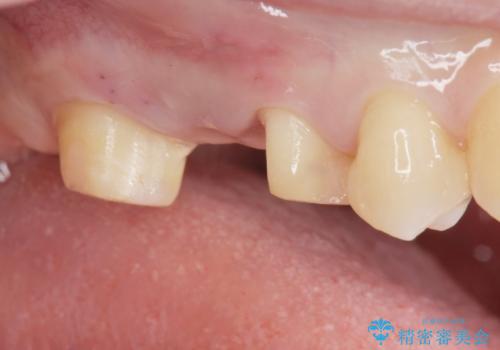

なので親知らずを抜歯して、一番奥の歯を部分矯正(upライト)をして倒れ込んでいる歯を起こしてスペースを作り、ブリッジの治療を行いました。